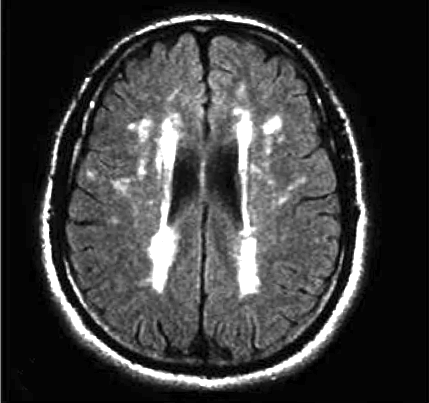

Il progredire della leucoaraiosi tende a seguire un modello generale. Inizialmente si osservano le lesioni periventricolari verso i bordi dei ventricoli laterali (Fig.1), estendendosi queste, in seguito e secondo la gravità del fenomeno, intorno ad essi (Fig.2).